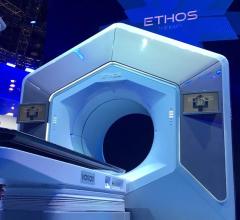

The University of Texas MD Anderson Cancer Center and Varian announced a new strategic collaboration to develop an integrated software platform to streamline review of radiation oncology treatment plans.